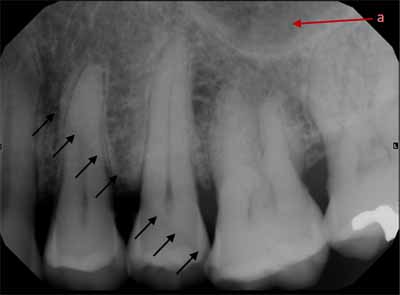

下顎の外側部に向かって後方に移動すると、犬歯、小臼歯、大臼歯が見えます。小臼歯と大臼歯の下には下顎管があり、薄いエックス線不透過性の境界に囲まれた幅広いエックス線透過性の線として現れます。下顎管は下顎の頬側表面にあるオトガイ孔に開口しています。口腔内画像では、オトガイ孔は小臼歯の根尖のすぐ下またはその高さにある丸いエックス線透過性の構造として確認できます(画像 18 および 19 を参照) 。下顎管は下顎枝にあるオトガイ孔から下顎孔まで下顎の外側部分全体に沿って走っています。多くの場合、臼歯の根尖のすぐ下か、同じ高さに位置します。等角投影と軸測投影の両方で、臼歯の頂点に重なって描かれることもあります(画像20と21を参照)。

オトガイ孔の画像では、下顎骨の基底部が見えることも珍しくありません。これは下顎の下縁を形成する、強いエックス線不透過性の線として現れます (画像20と21を比較)。